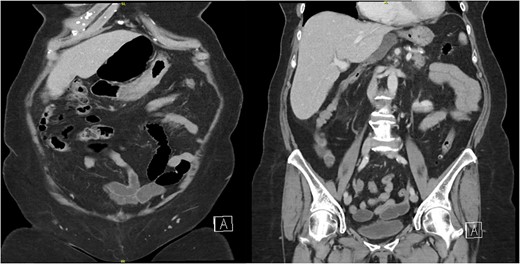

The patient’s laboratory values were significant for WBC 12.2 × 109/L, potassium 3.1 mmol/L, creatinine 0.59 mg/dl, lipase 676 U/L, total bilirubin 1.8 mg/dl, direct bilirubin of 0.6 mg/dL, ALT/AST 147/221 U/L, and alkaline phosphatase of 579 U/L. A computed tomography (CT) scan of the abdomen and pelvis with intravenous contrast demonstrated the cecum herniating through the foramen of Winslow with no signs of ischemia or bowel obstruction (Fig. 1); the gallbladder was distended with pericholecystic stranding and surrounding portal triad inflammation (Fig. 2).

A computed tomography (CT) scan of the abdomen and pelvis with intravenous contrast demonstrating a distended gallbladder with pericholecystic stranding and surrounding portal triad inflammation.